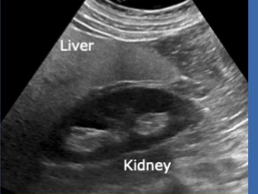

Echogenicity of this

Kidney = hypoechoic to liver

Liver = hyperechoic to kidney